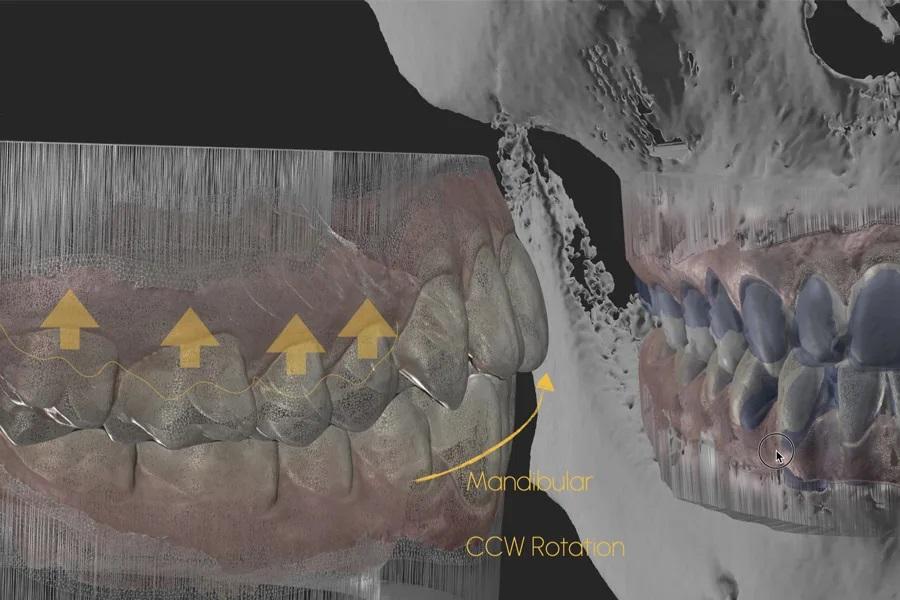

Фото 9. Функциональное планирование: цифровое моделирование противочасовой авторотации нижней челюсти пр. ч. с. в центральном соотношении (отслеживание движения челюсти) с учетом дентофациальных ориентиров.

Интрузия боковых зубов (например, примерно на 2–3 мм в области моляров) моделируется для определения авторотации нижней челюсти пр. ч. с. с обеспечением адекватного переднего ведения и функционального пространства движений. Использование гибридных (аналогово-цифровых) или полностью цифровых методов отслеживания движений нижней челюсти/аксиографии повышает точность определения конечного положения нижней челюсти по завершении лечения (фото 9 – 12).